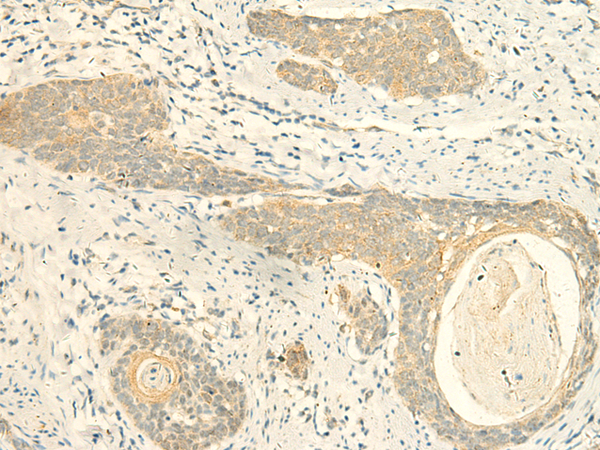

IHC positive control: |

Human esophagus cancer |